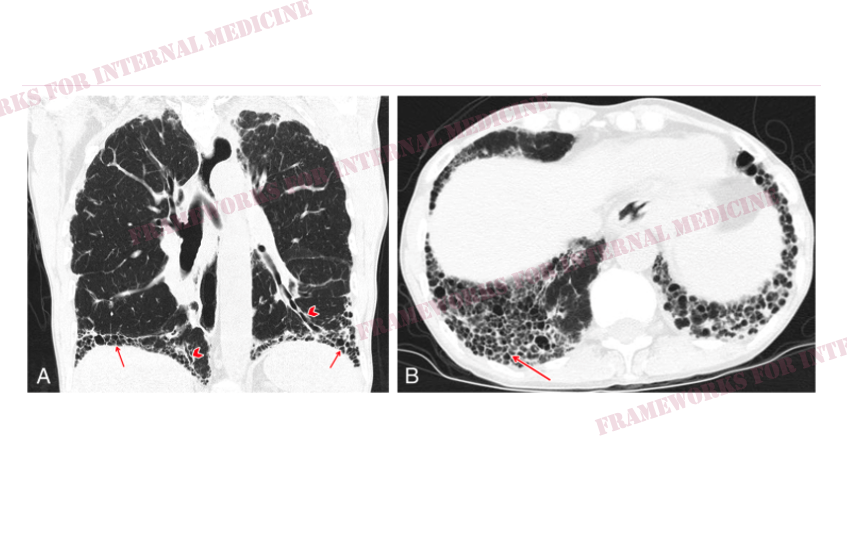

High res CT demonstrates lower lobe–predominant subpleural reticular opacities and honeycombing (arrows), traction bronchiectasis (arrowheads), and no ground glass

The pattern on HRCT imaging is UIP, a common presentation of ILD associated with scleroderma.